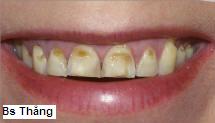

![]() ![]() | Mòn mặt trước và rìa cắn do tiếp xúc với acid qua không khí lâu dài |